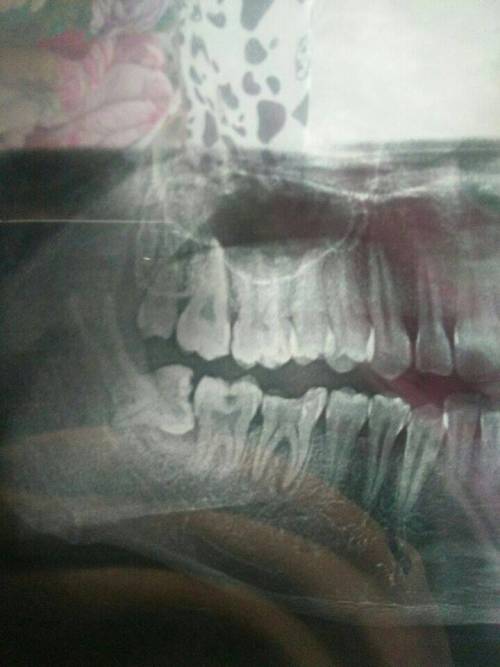

1、術(shù)前檢查:拔智齒前需要進(jìn)行口腔檢查、X光片等檢查,以了解智齒的位置和周?chē)Y(jié)構(gòu),這些檢查費(fèi)用也是拔智齒總費(fèi)用的一部分。

1、智齒位置:智齒的位置是影響拔除費(fèi)用的重要因素之一,智齒的位置越深,手術(shù)難度越大,拔除費(fèi)用也就越高。

2、手術(shù)復(fù)雜性:拔智齒手術(shù)的復(fù)雜性也會(huì)影響費(fèi)用,如果智齒生長(zhǎng)位置正常,手術(shù)相對(duì)簡(jiǎn)單;如果智齒被埋在骨頭里,需要切開(kāi)牙齦和骨頭,手術(shù)難度增大,費(fèi)用相應(yīng)增加。